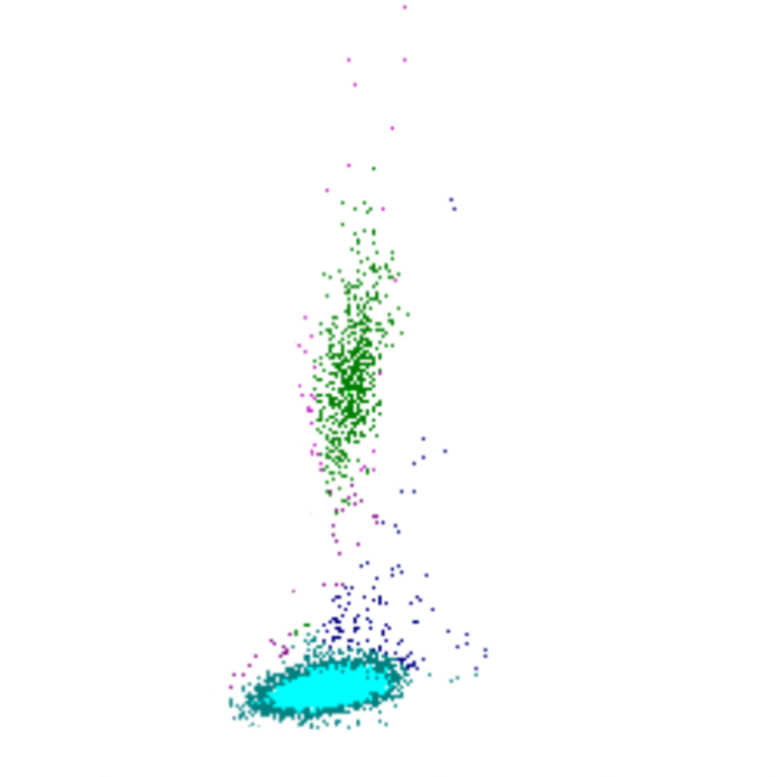

Side Fluorescence

Le signal SFL reflète la teneur en acides nucléiques des cellules. Les cellules avec un SFL élevé contiennent davantage d’ARN et/ou d’ADN, ce qui indique souvent une activité ou une prolifération accrue. Il existe une corrélation limitée entre le SFL et le FSC ; bien que les cellules plus grandes présentent généralement un SFL plus élevé, des exceptions existent, telles que des blastes avec un SFL relativement faible ou des lymphocytes activés avec un SFL élevé malgré leur plus petite taille.